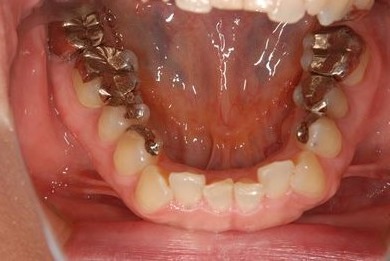

主訴 噛むと痛い。(咬合痛がある)

治療前

• 治療前